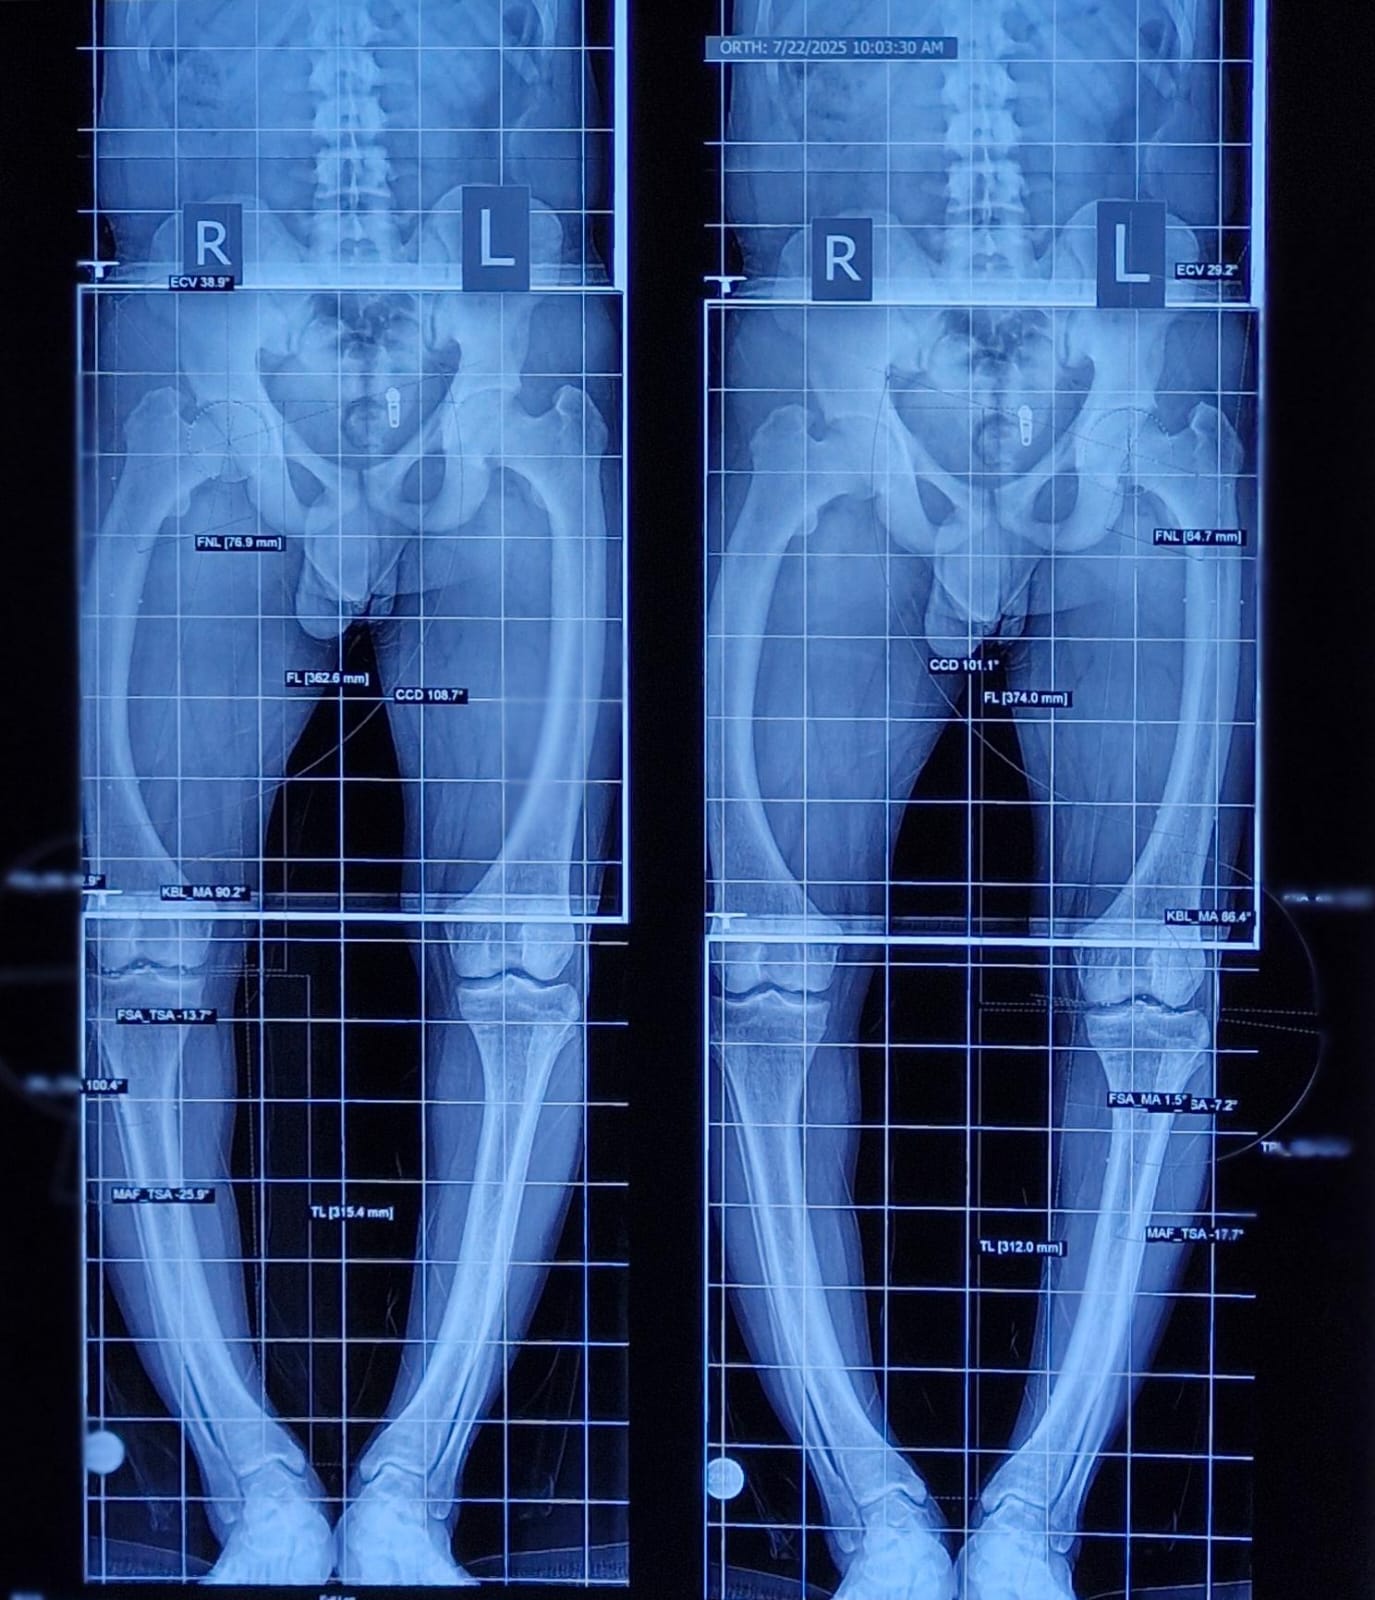

Knock Knees, also known as genu varum, is a condition where the legs appear bowed outwards when standing. This condition can cause discomfort, pain, and even difficulty walking. In severe cases, surgery may be required to correct the alignment of the legs. In this article, we will discuss the causes, symptoms, and treatment options for Knock Knees, including the various surgical procedures available.

A doctor can diagnose knock knees by performing a physical examination and assessing the alignment of the legs. Imaging tests such as X-rays or MRI scans may also be used to confirm the diagnosis.